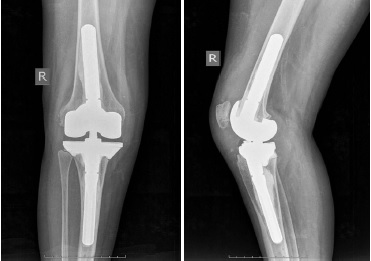

Finally, prosthetic components were implanted using the bone cement (Fig.4). Two doses of bone cement in combination with thermoresistant antibiotics were applied to prevent infectious complications. Then the range of motions was checked, the joint stability was evaluated, the wound was sutured layer-by-layer and knee X-rays in two views were taken (Fig. 5).

Fig. 4. The implanted individual endoprosthesis components

Fig. 5. Postoperative X-rays of the right knee in direct and lateral projections